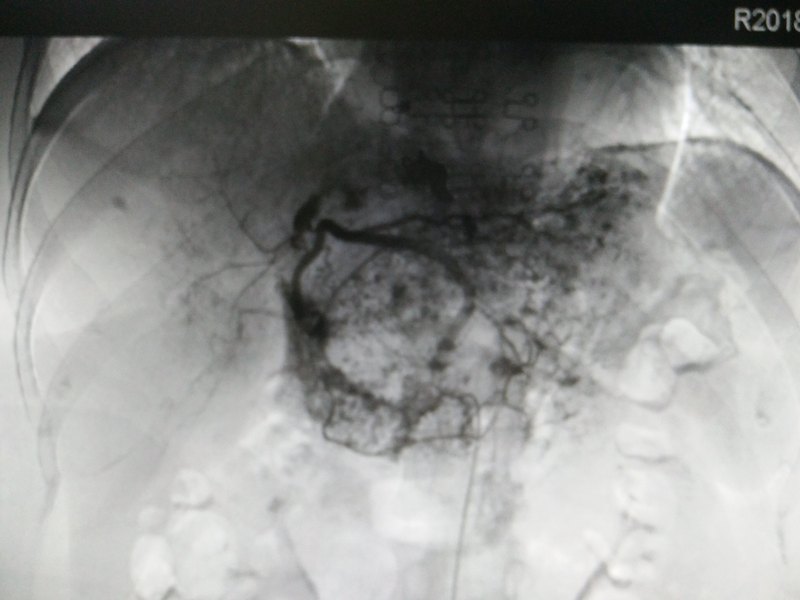

患者男性,50余歲,肝炎后肝硬化,反復(fù)上消化道出血病史四年,于當(dāng)?shù)蒯t(yī)院反復(fù)行套扎,硬化治療多次,仍反復(fù)多次出血,幾經(jīng)周折來到我們科室行TIPS治療 術(shù)后飲食小貼士: 1、減少產(chǎn)氨物質(zhì)的攝入(主要是蛋白類失誤),記住是減少,不是不能吃,只要控制好每日蛋白的攝入總量——即低蛋白飲食 2、促進(jìn)體內(nèi)血氨的排泄,多吃新鮮蔬菜水果。